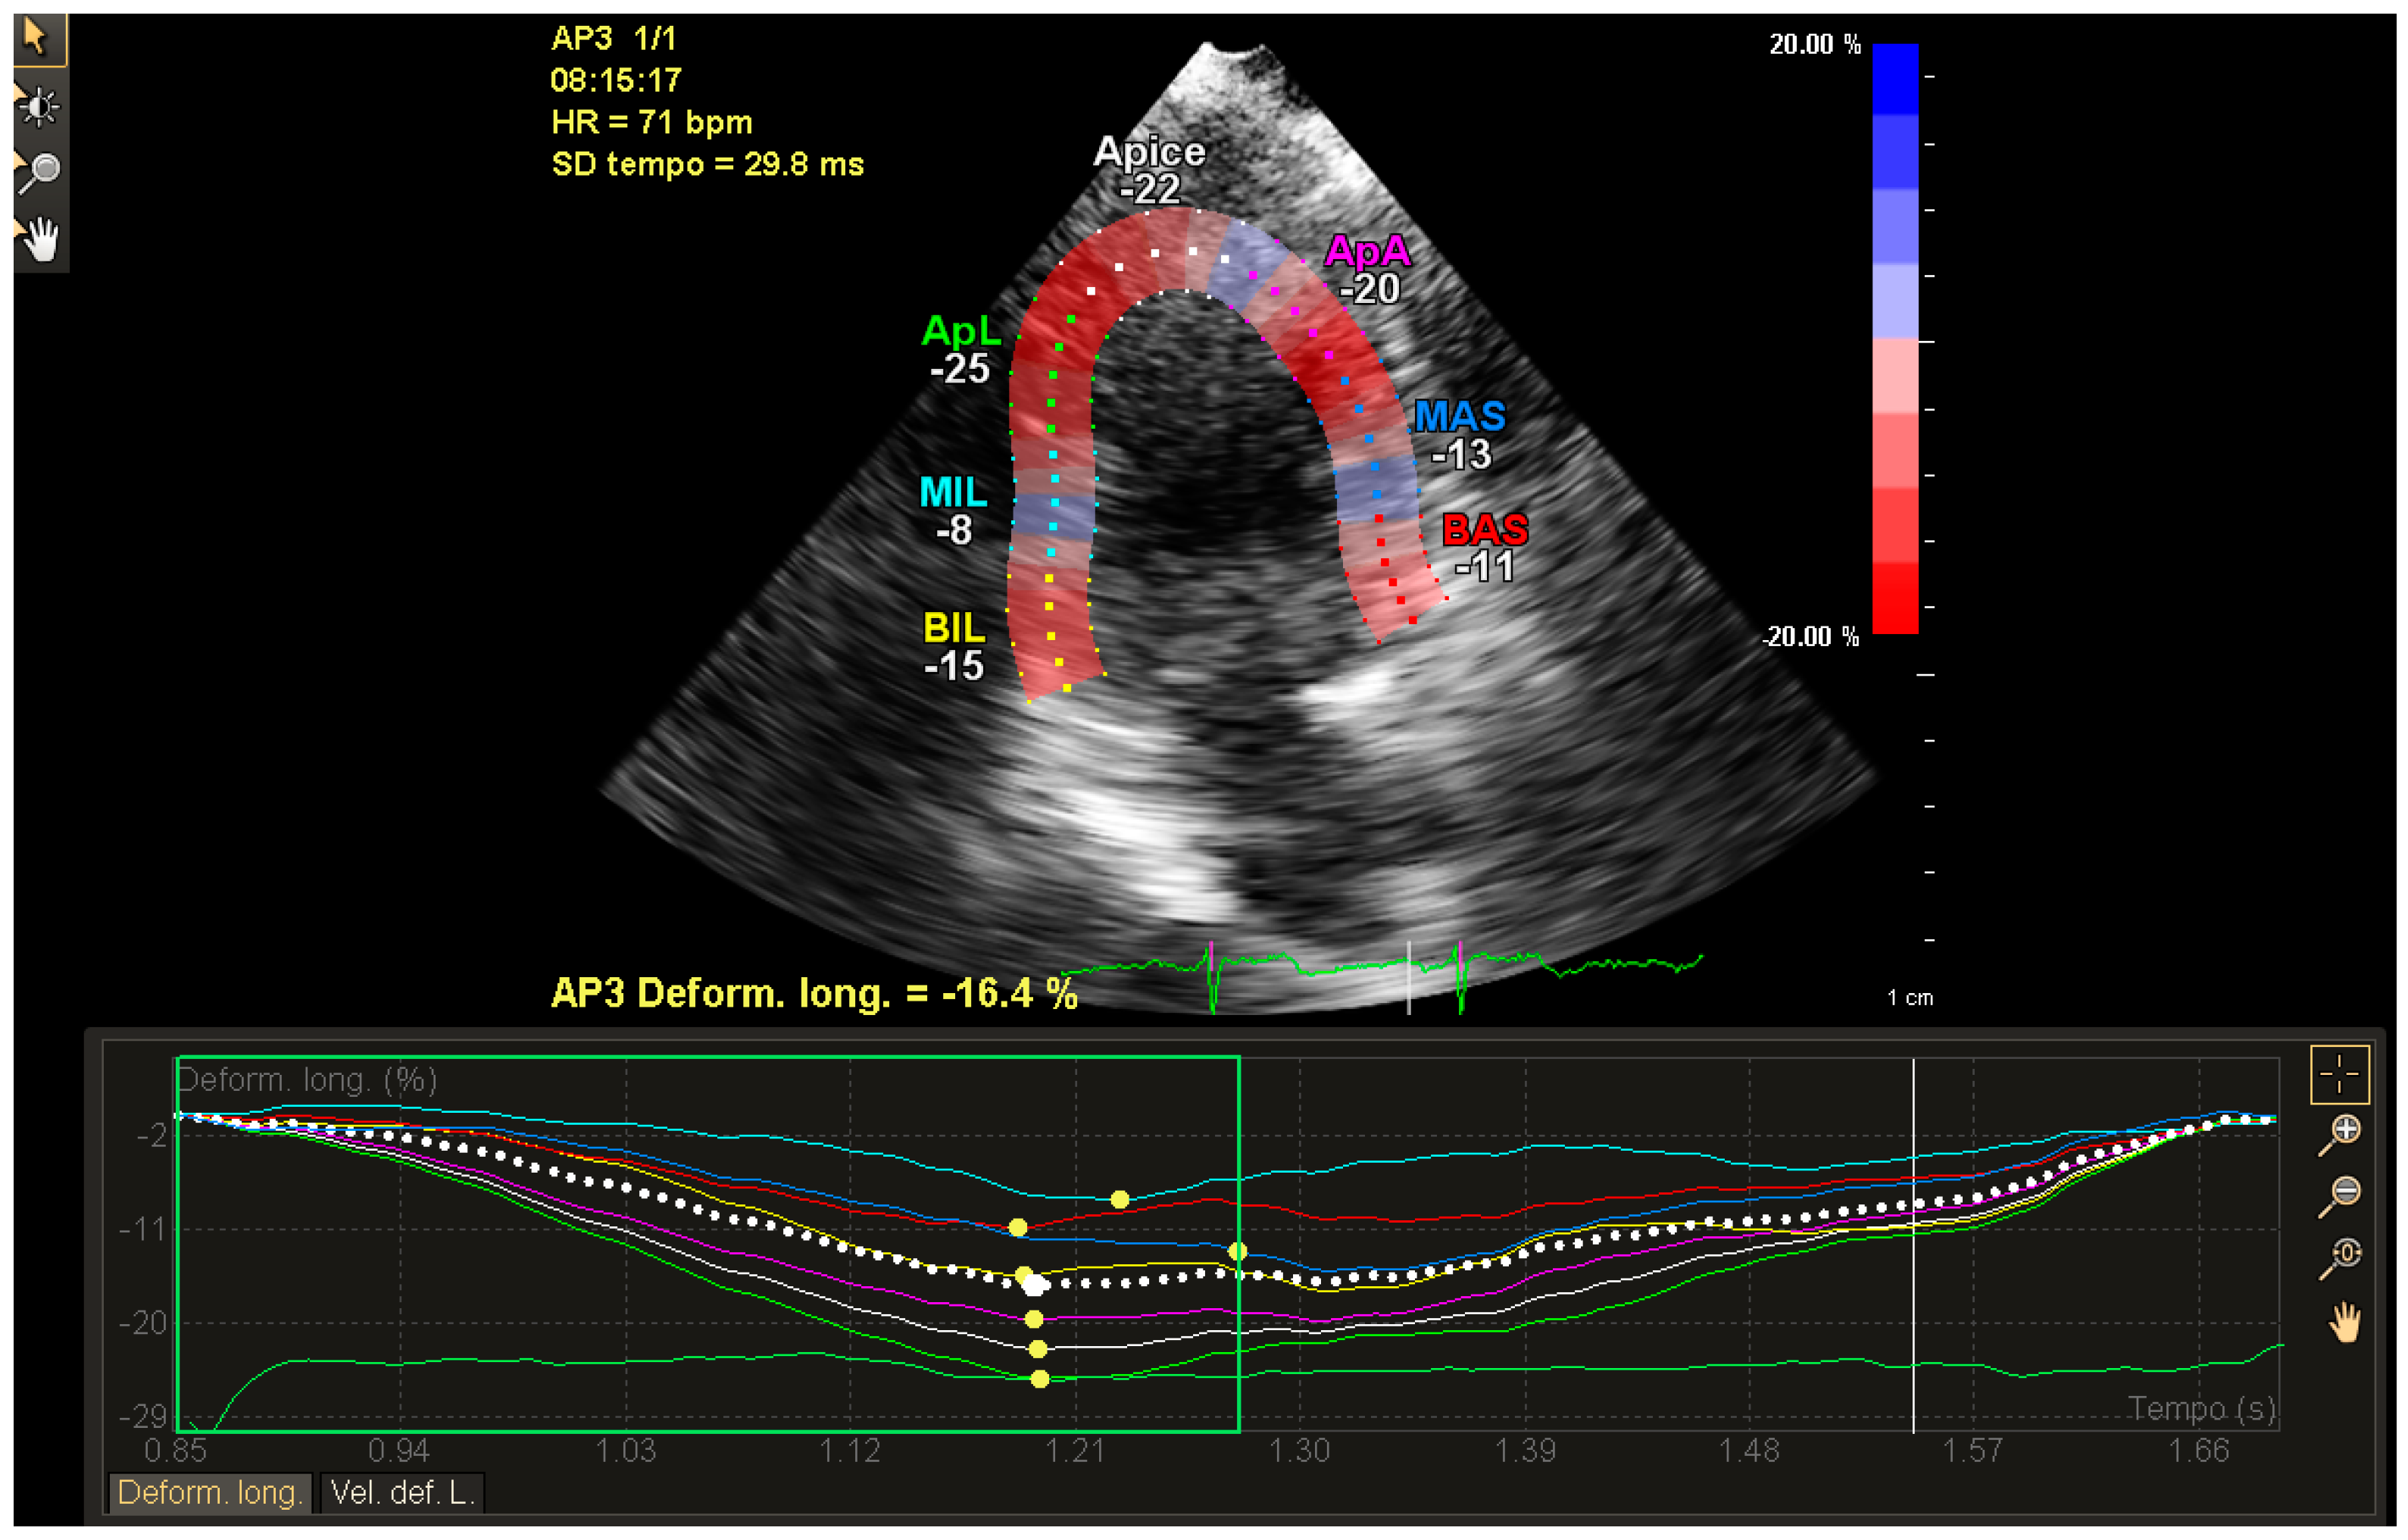

2. Technical Considerations for Strain Analysis

3. Clinical Applications of Strain for the Early Clinical Detection of Myocardial Damage

4. Strain in Cardio-Oncology